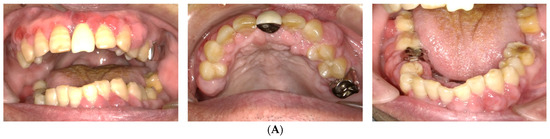

At the first examination, the patient’s gingiva showed generalized redness and bleeding with spontaneous pain (Figure 1). Prominent bleeding and discharge of suppuration were observed in the gingiva. The interdental papillae exhibited crater-shaped ulcerations. Severe oral halitosis was present. Physical examination findings were as follows: body temperature, 36.7 °C; blood pressure, 142/60 mmHg; and heart rate, 84 beats/min. The initial blood test indicated the following: white blood cell count, 6500/μL; platelet count, 22.8 × 104/μL, total protein (TP); 6.9 g/dL, C-reactive protein (CRP); 0.14 mg/dL, prothrombin time (PT), INR, 1.2; activated partial thromboplastin time (APTT), 40 s; and HbA1c, 6.0%.

Figure 1.

Intraoral photos taken at the patient’s first visit reveal generalized gingival redness, swelling, and bleeding.